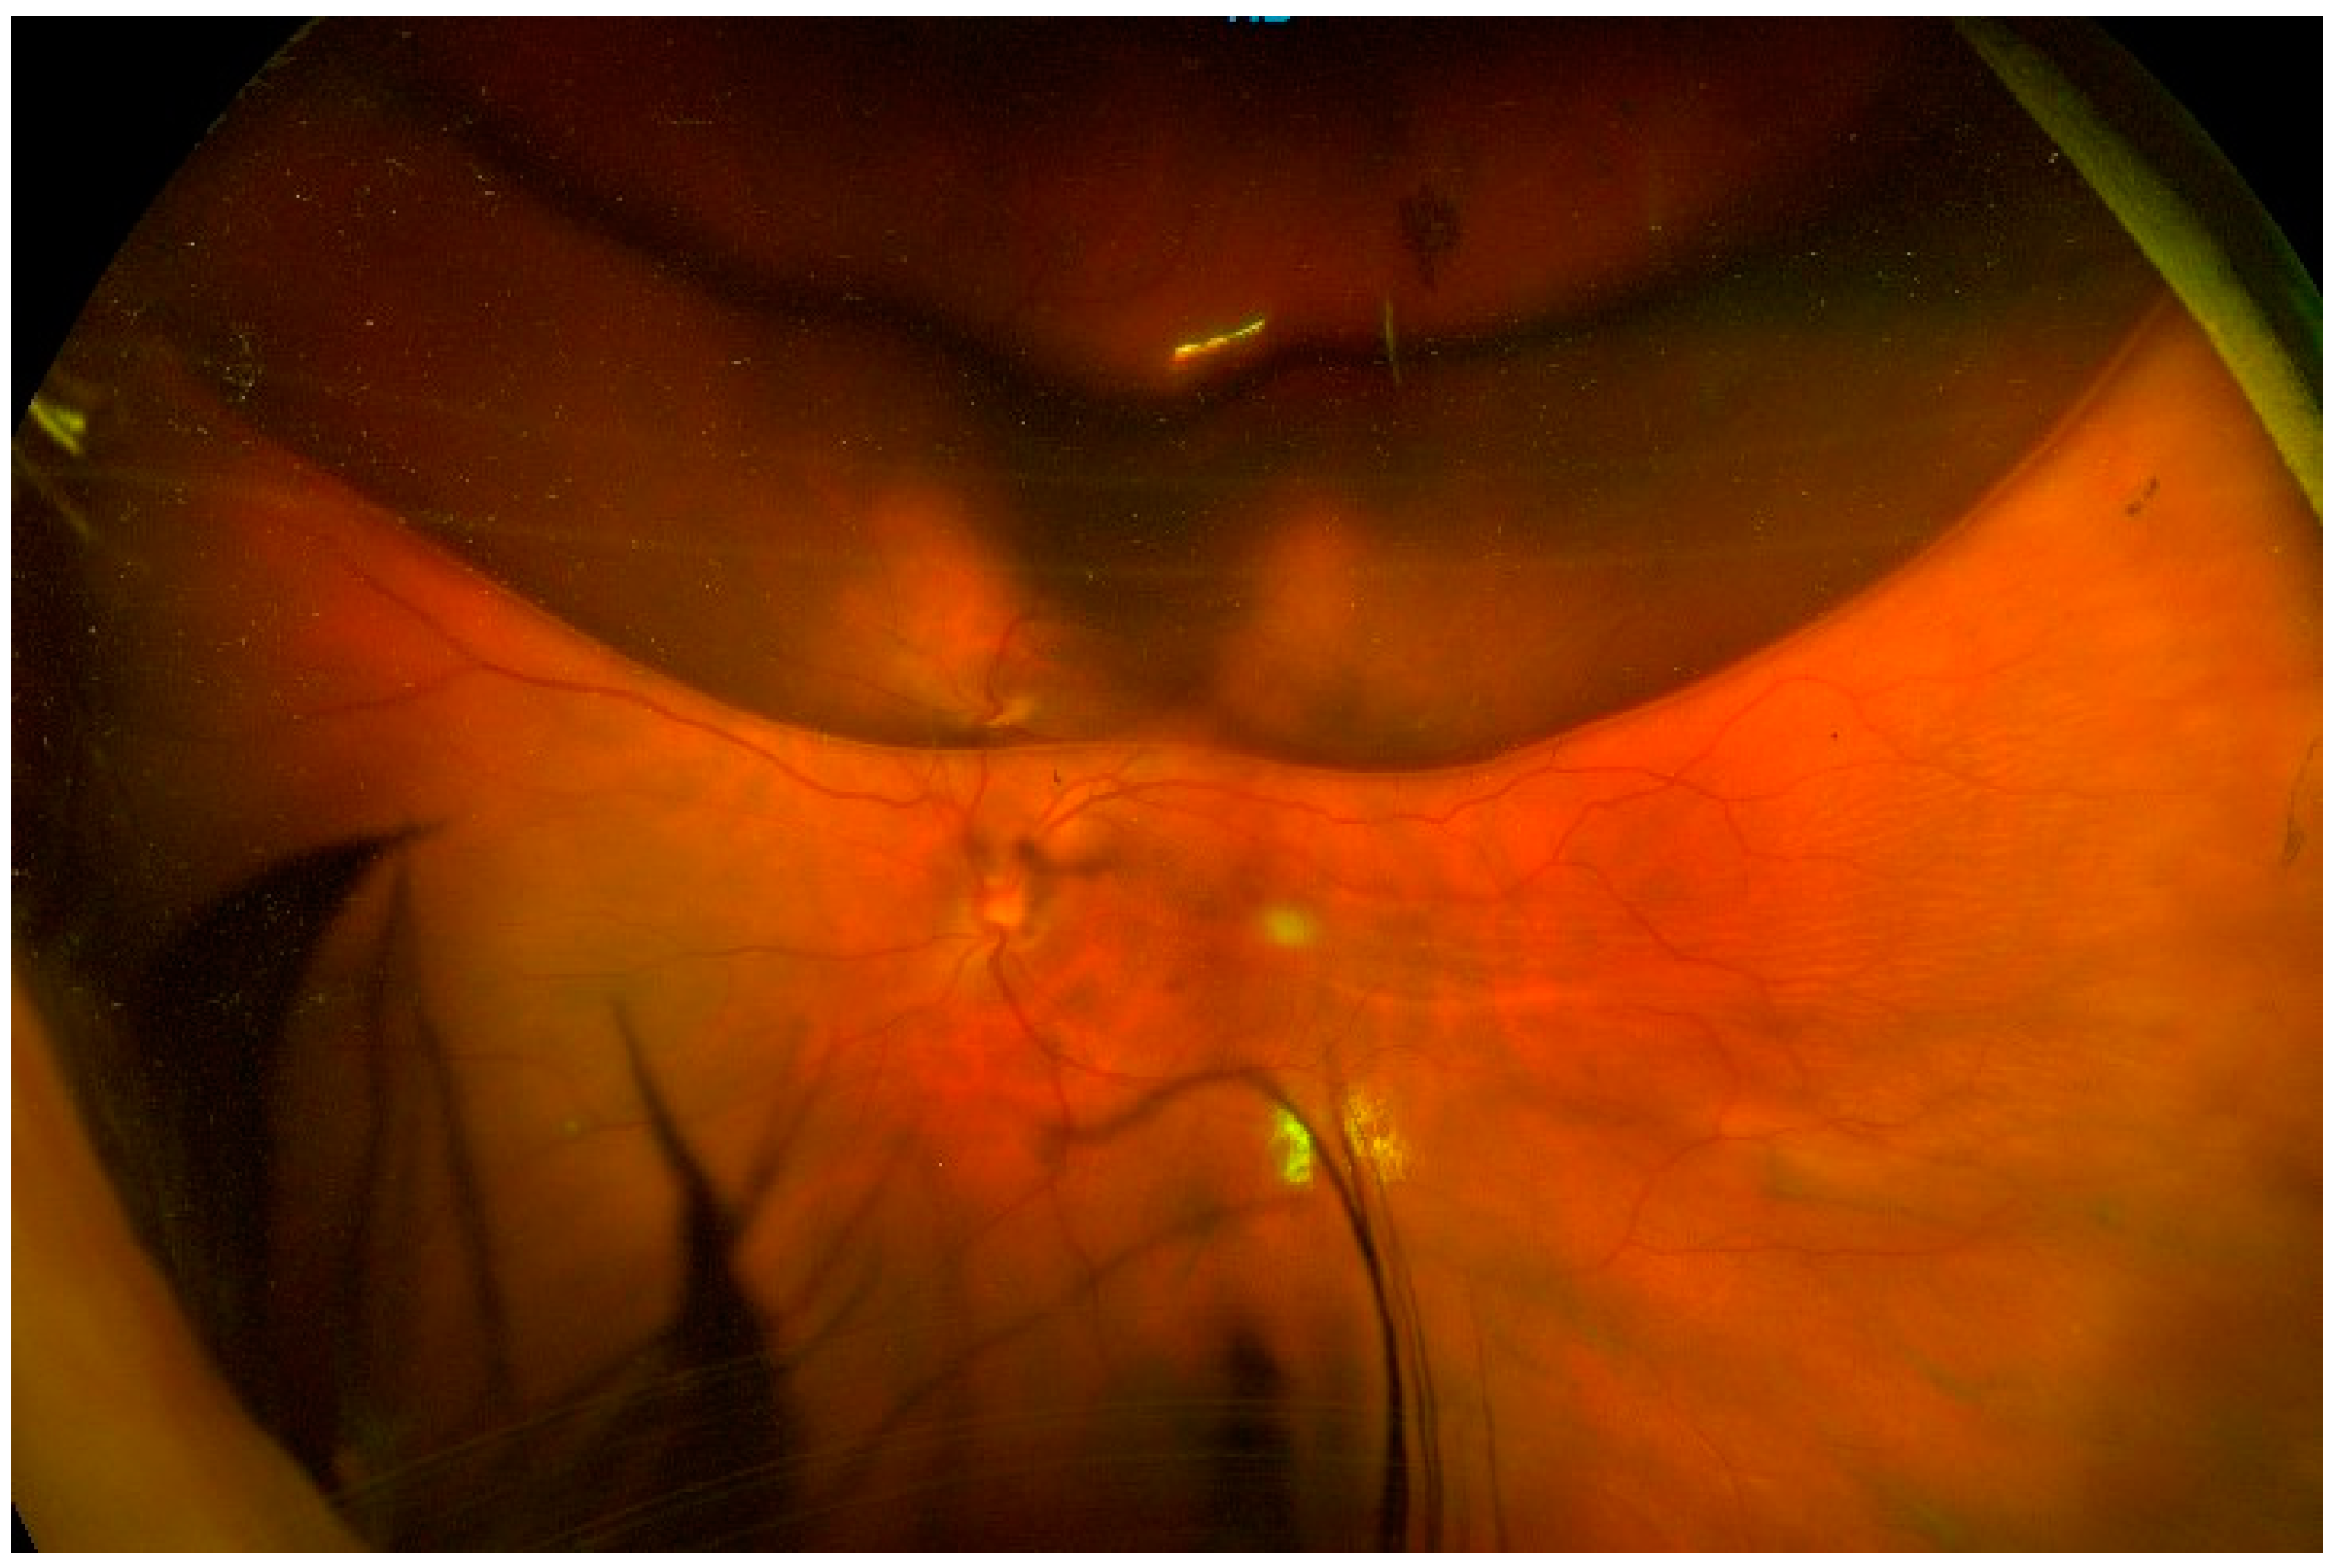

Figure 1. Pre-operative fundus picture. Left eye, superior RRD (white arrow) with a large retinal break at 12–1 o’clock (red arrow).

The patients analyzed in this work suffered from macula-on, treatment-naïve rhegmatogenous retinal detachment, which involved the superior, temporal, and/or nasal quadrants. The retinal breaks had to be in the superior meridians (between 10 o’clock and 2 o’clock) (Figure 1). They could be pseudophakic or phakic patients with a grade ≤ 2 cataract in Thompson grading [28] and in any refractive status, including high myopia. A mild localized vitreous hemorrhage was tolerated as long as the optic disk, the retinal vessels, and the whole periphery were clearly visible.